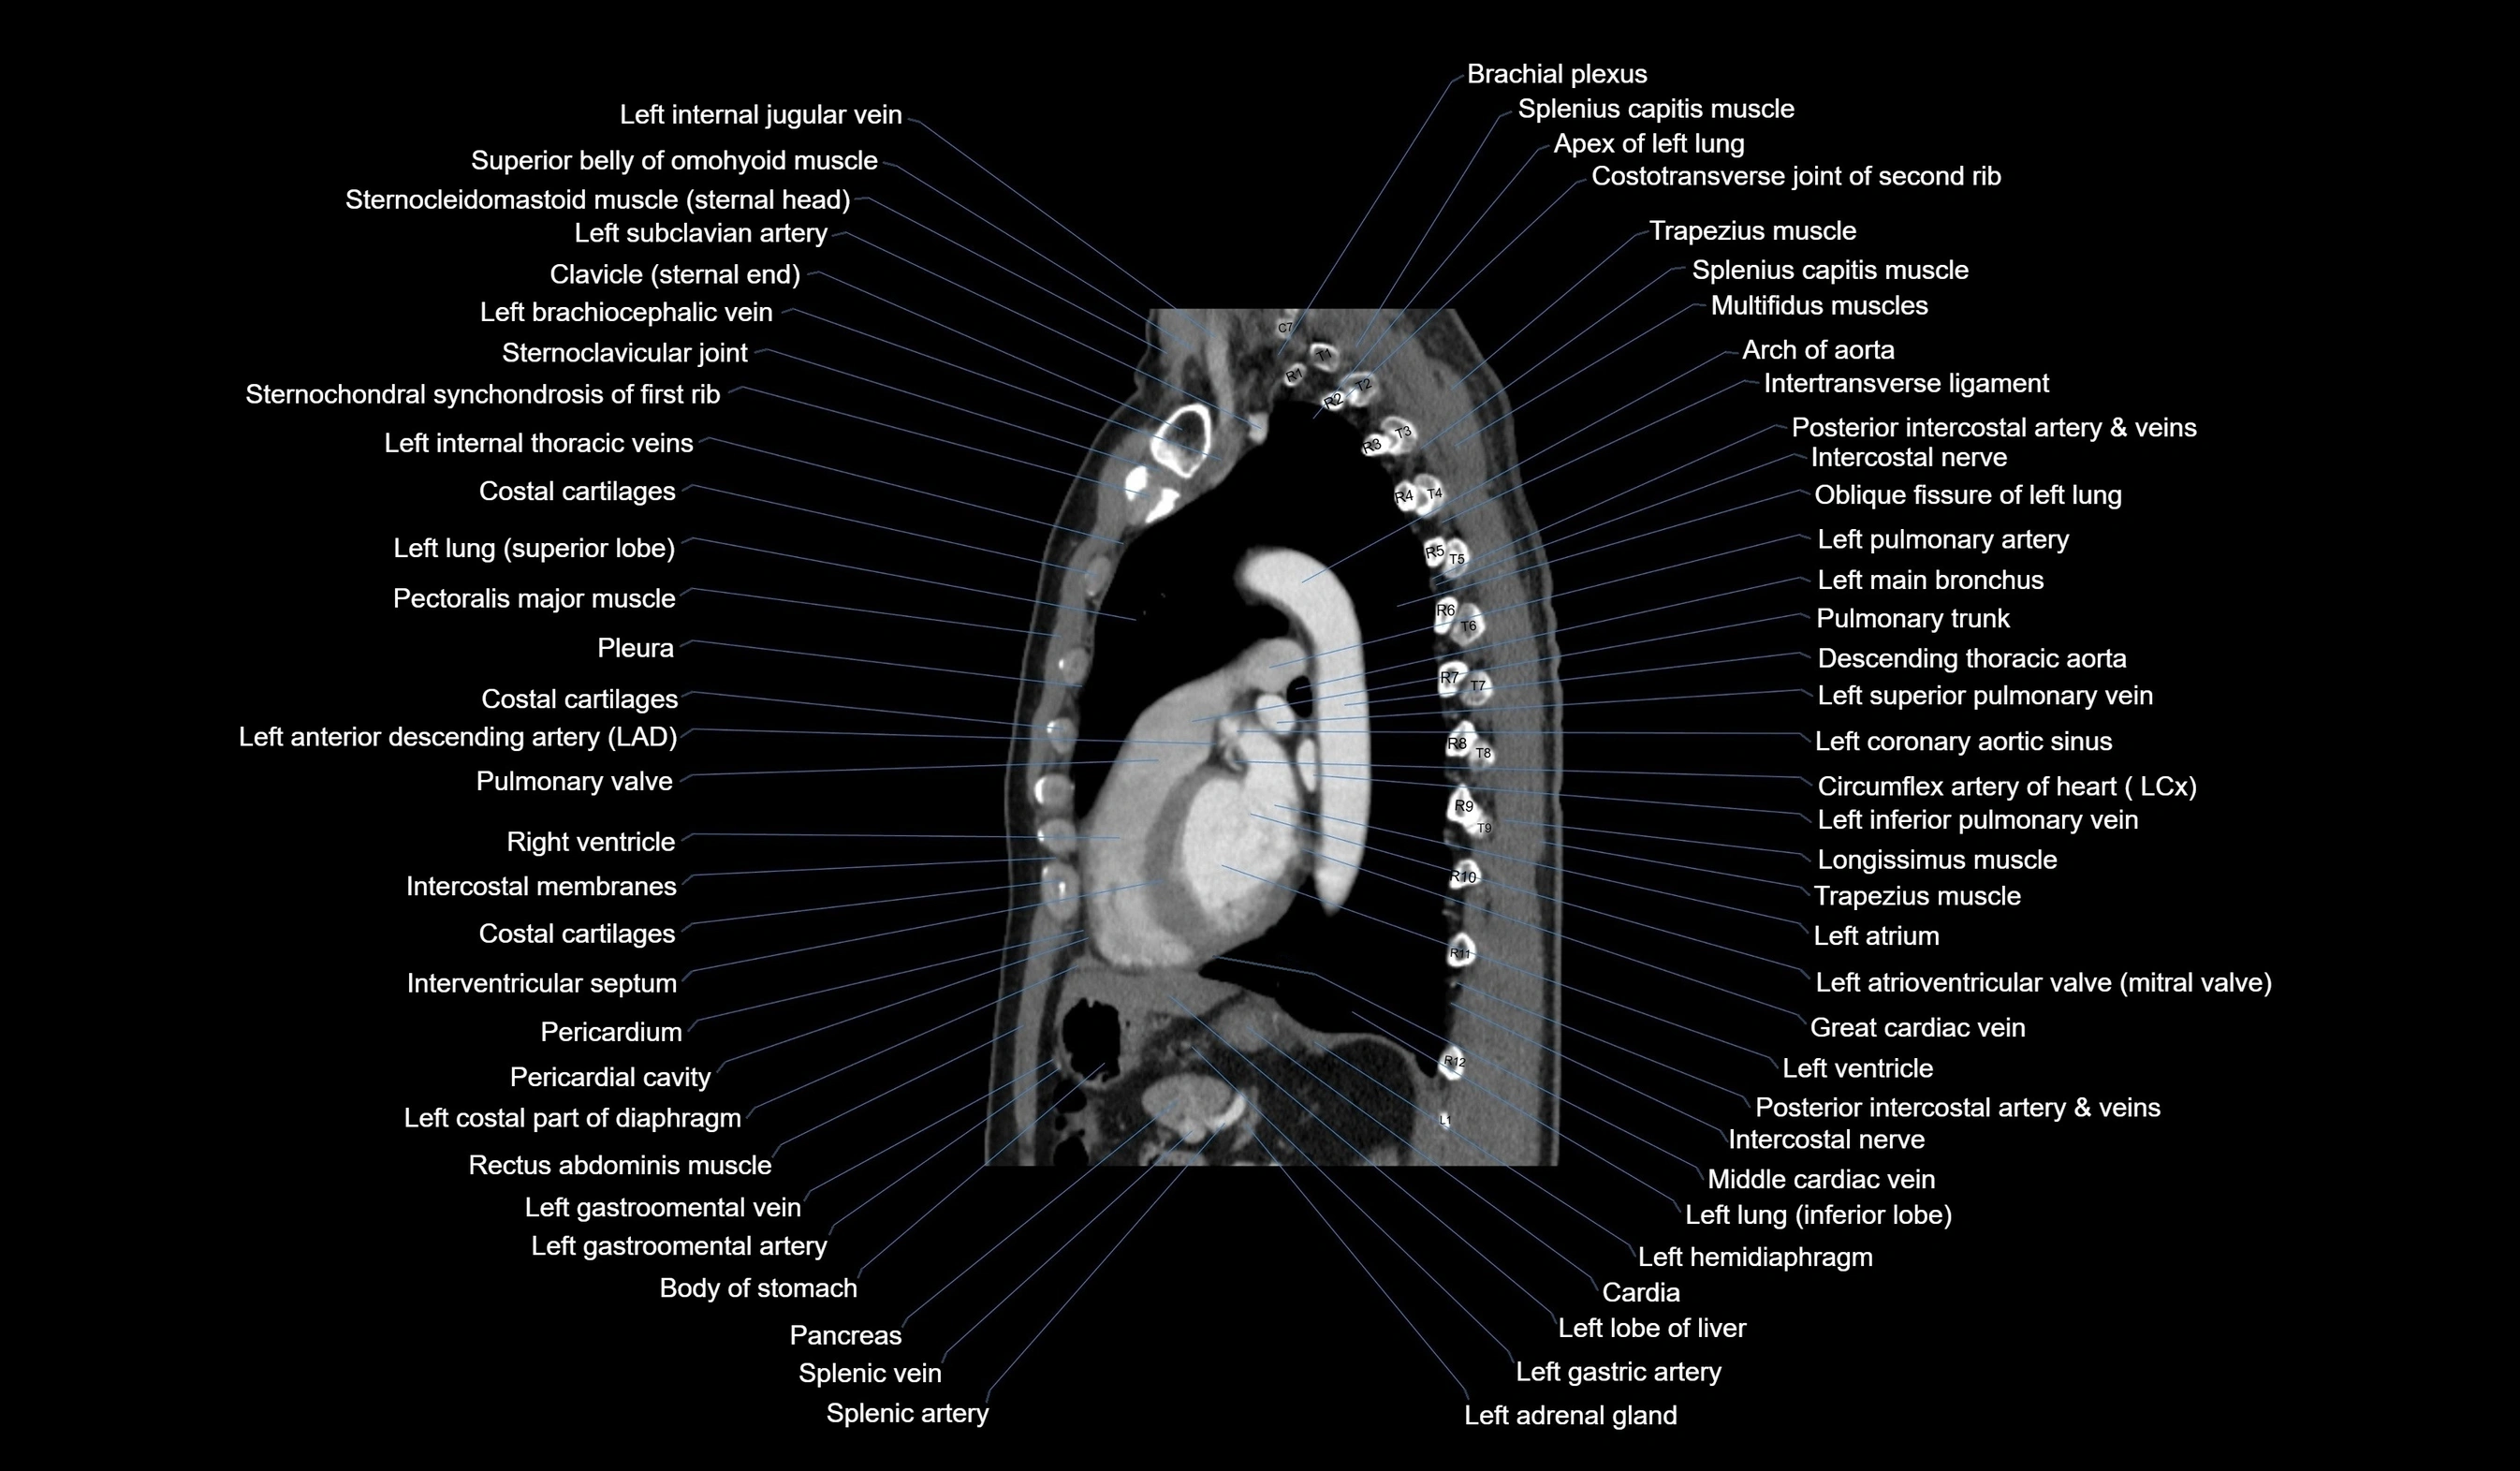

CT images